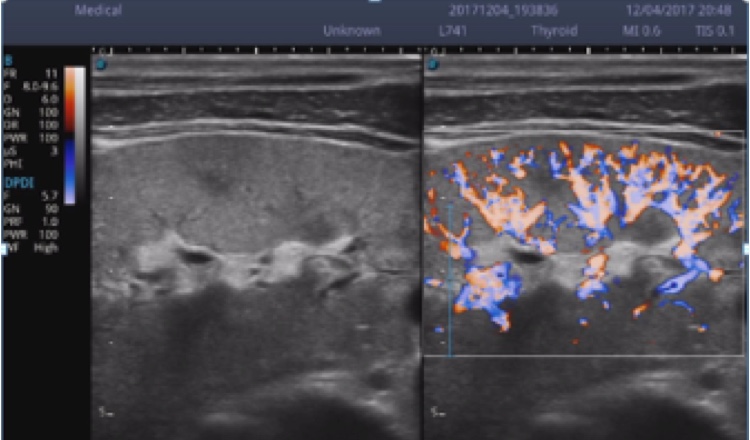

X5采用前端的超声专用芯片,将台式机大规模集成电路完美压缩在笔记本超声的精巧下,提高了系统的运算速度,加载μ-Scan微米成像、脉冲反相谐波等技术,带来优异的临床表现,清晰呈现高分辨率二维图像和层次丰富的血流图像

X5具备实时宽景成像、穿刺增强、彩色M型、组织多普勒等多种高级成像功能,全方位满足多个科室的诊断需求,整机系统向智能化跨越